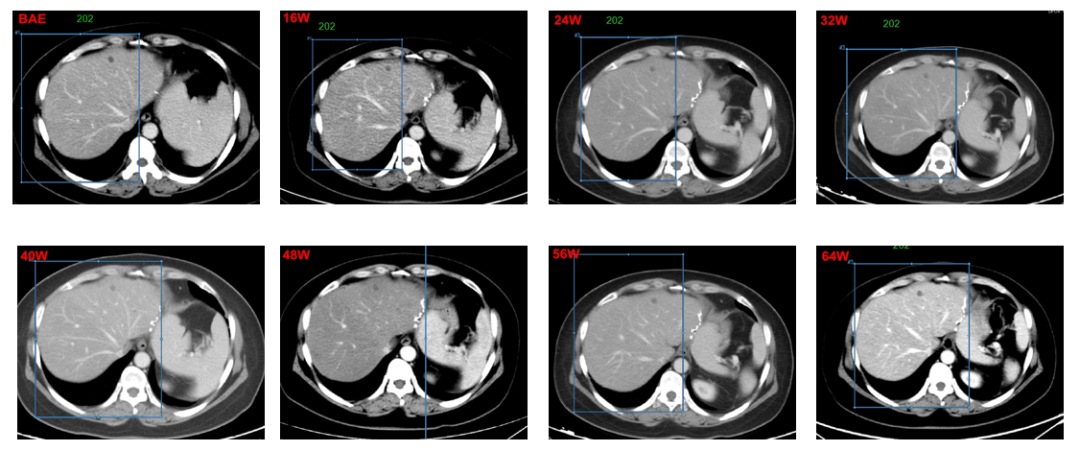

2号非靶病灶位于肝右叶,8w-64W被评为SD